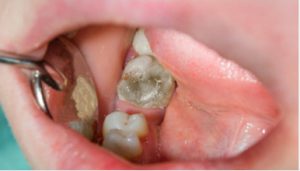

·浮雕成像技術提升神經清晰度300%

·精準診斷牙體牙髓病孌

·德國原廠40年X線技術背書

德國迪珥齒科牙片寶